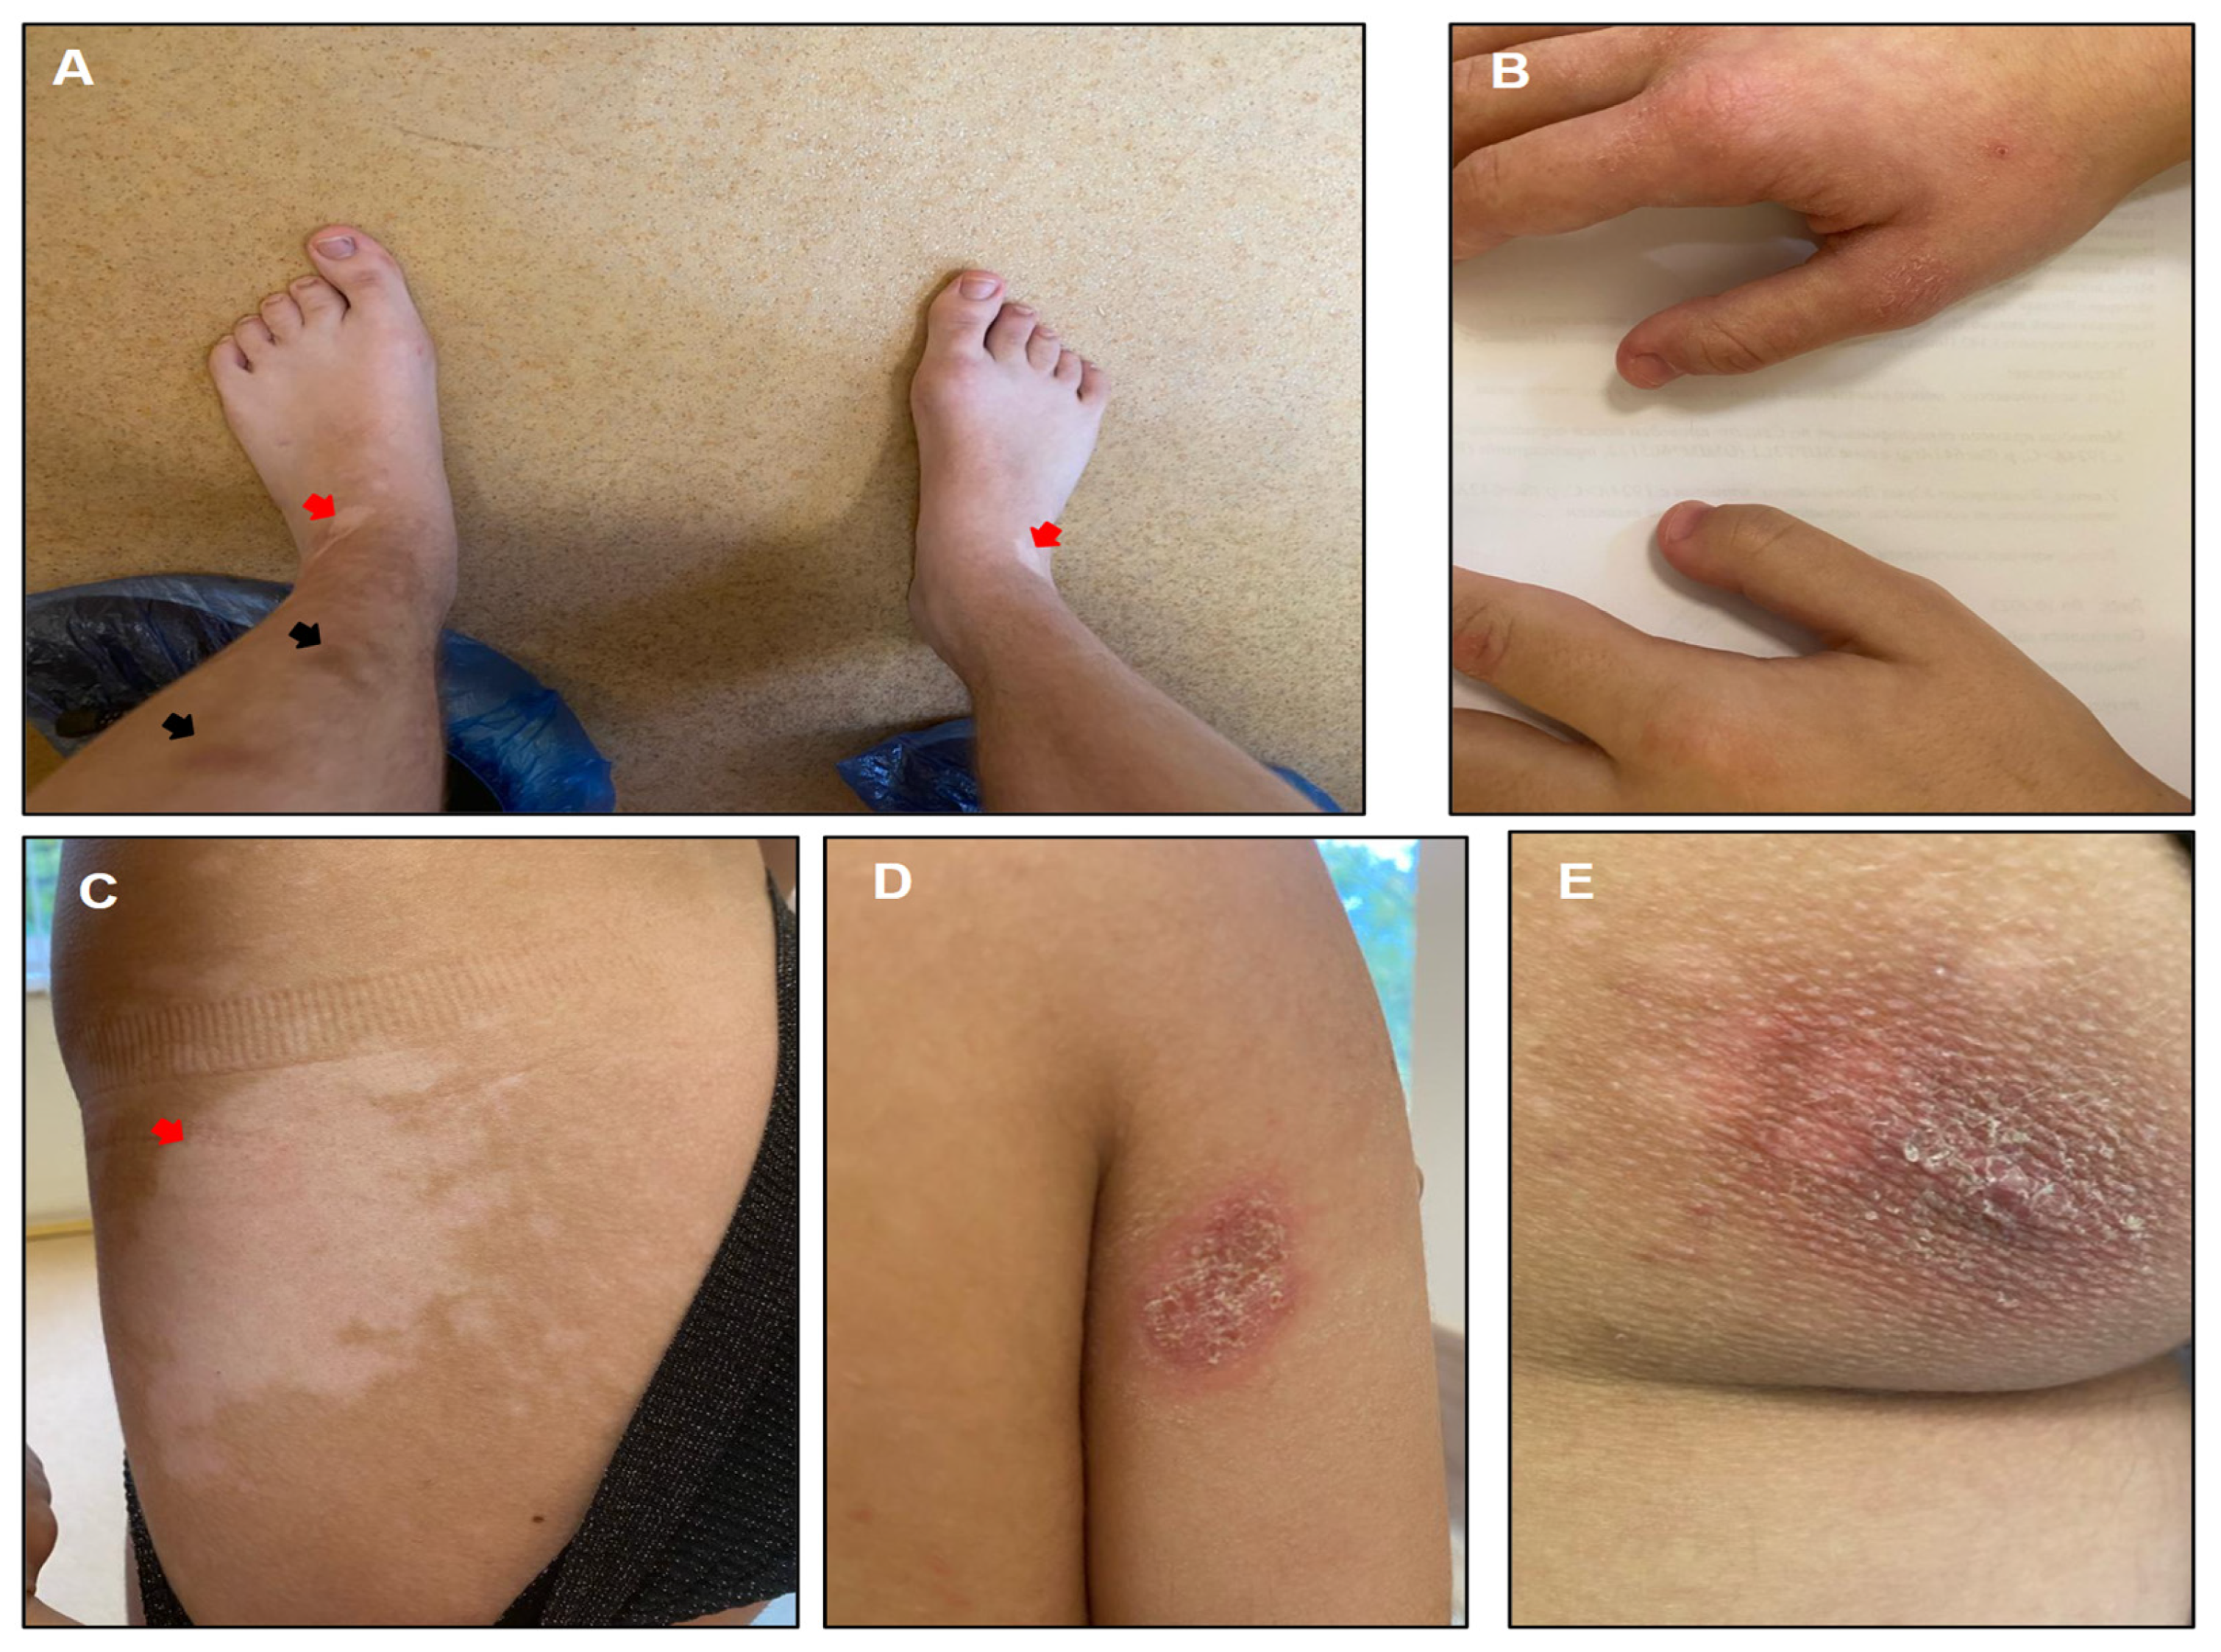

3.1. Clinical Case

3.2.3. Evaluation at 17 Years Old